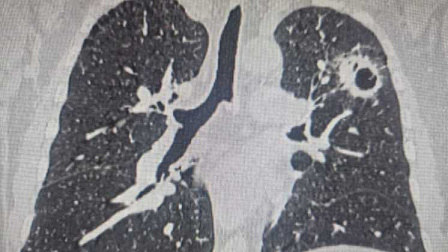

Креветки помогли учёным Новосибирска найти способ улучшить борьбу с раком

Белок из глубоководной креветки сильнее «подсветит» опухолевые клетки, а значит многократно повысит точность специальной адресной терапии